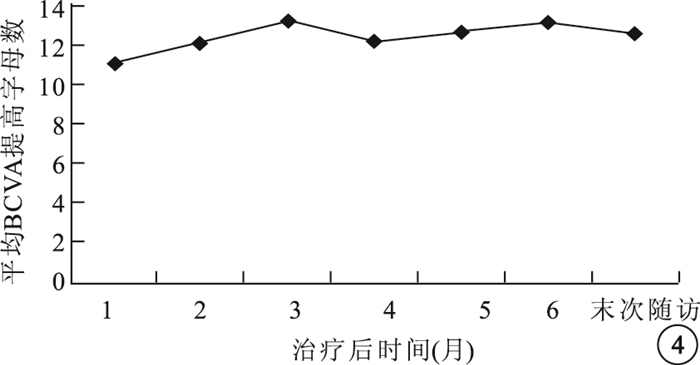

治療后1、3、6個月及末次隨訪時,患眼平均BCVA分別為(52.30±21.16)、(54.45±20.47)、(54.30±19.86)、(53.00±20.21)個字母,較治療前分別提高了(11.10±8.49)、(13.25±8.35)、(13.10±7.87)、(11.80±7.27)個字母,差異均有統計學意義(t=5.85、7.09、7.44、7.25,P<0.01)(圖 4)。治療后1個月視力顯著提高6只眼,占30%;提高8只眼,占40%;穩定6只眼,占30%;末次隨訪時,視力顯著提高6只眼,占30%;提高9只眼,占45%;穩定5只眼,占25%。

圖4

治療后不同時間患眼平均BCVA提高字母數比較

治療后1、3、6個月及末次隨訪時,患眼平均BCVA分別為(52.30±21.16)、(54.45±20.47)、(54.30±19.86)、(53.00±20.21)個字母,較治療前分別提高了(11.10±8.49)、(13.25±8.35)、(13.10±7.87)、(11.80±7.27)個字母,差異均有統計學意義(t=5.85、7.09、7.44、7.25,P<0.01)(圖 4)。治療后1個月視力顯著提高6只眼,占30%;提高8只眼,占40%;穩定6只眼,占30%;末次隨訪時,視力顯著提高6只眼,占30%;提高9只眼,占45%;穩定5只眼,占25%。

圖4

治療后不同時間患眼平均BCVA提高字母數比較